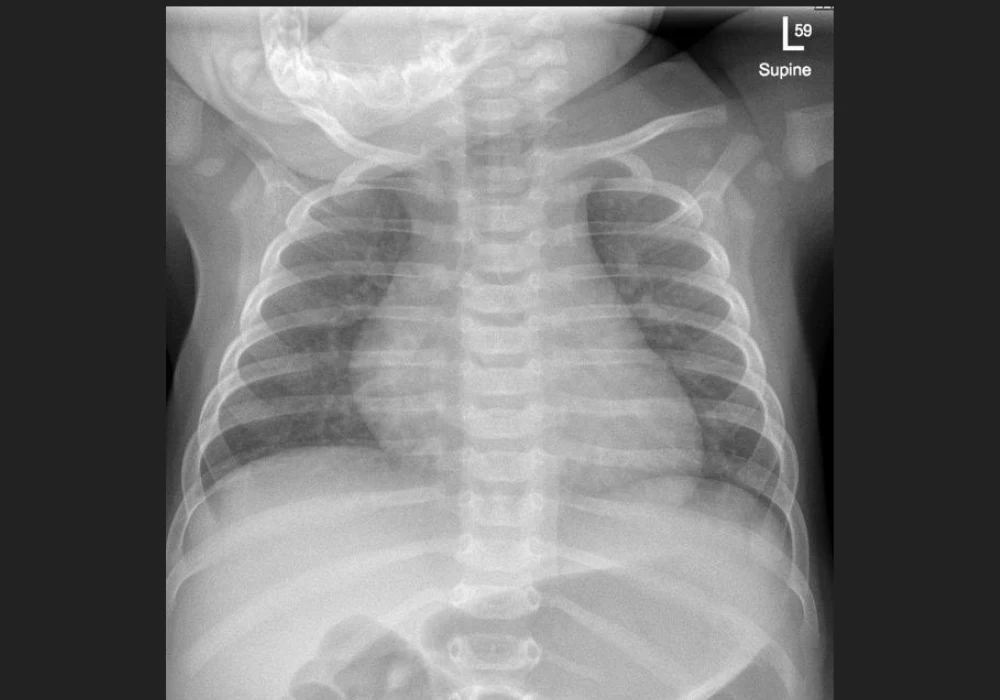

Automated reading of chest x-rays (CXR) using computer-aided detection (CAD) is recommended for adults in tuberculosis (TB) screening and triage, yet paediatric use remains unaddressed. Childhood TB presents distinct clinical and radiographic patterns, CXR interpretation is variable, and image acquisition in young children is technically challenging. As CXR is often the only adjunctive test available in primary care, there is a clear need for paediatric-specific CAD that can recognise age-related anatomy, typical TB features and common differentials. Progress depends on building suitable data resources, adapting modelling approaches to children and resolving analytical and implementation issues that affect accuracy, equity and practical use.

High-quality paediatric repositories are the foundation for effective models. Image sets should prioritise children younger than 10 years, represent diverse geographies and TB burdens and include infants, children living with HIV and those with malnutrition. They should capture the breadth of pathology relevant to TB—such as hilar lymphadenopathy, consolidation, airway compression, pleural effusion and cavitation—alongside non-TB conditions and normal developmental variation, including the presence or absence of the thymus. Variation in hardware, acquisition techniques and image quality is important to reflect real-world practice and reduce bias against underserved populations. Lateral-view CXRs, valuable for assessing hilar lymphadenopathy, should be included even though most commercial systems are not currently trained in this view.

Early paediatric CAD efforts for CXR abnormalities achieved moderate accuracy, with weaker performance in basal and perihilar regions that matter for TB. Deep learning models trained for paediatric pneumonia classification demonstrate good discrimination, but many compare diseased with normal images, which can overestimate real-world performance. Evidence specific to TB underscores the gap: a commercial TB CAD model in South African children initially achieved an area under the curve (AUC) of 0.58 for expert-defined TB consistency, improving to 0.72 after fine-tuning on paediatric images, for confirmed versus unlikely TB, AUC improved from 0.68 to 0.78 after fine-tuning. In Gambian children, against a microbiological standard, AUC reached 0.70 with high specificity at the manufacturer threshold but low sensitivity. Adjusting to 90% sensitivity markedly reduced specificity, highlighting the trade-offs and the need for paediatric-appropriate thresholds.